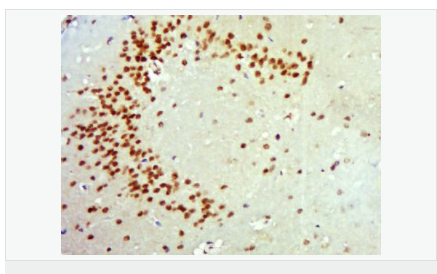

| 产品应用 | WB=1:500-2000 ELISA=1:5000-10000 IHC-P=1:100-500 IHC-F=1:100-500 ICC=1:100-500 IF=1:100-500 (石蜡切片需做抗原修复) not yet tested in other applications. optimal dilutions/concentrations should be determined by the end user. |